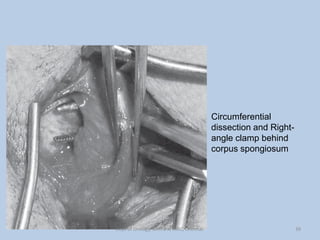

Circumferential

dissection and Right-

angle clamp behind

corpus spongiosum

Circumferential dissection and Right- angleclamp behind corpus spongiosum 39 Dept of Urology, GRH and KMC, Chennai.